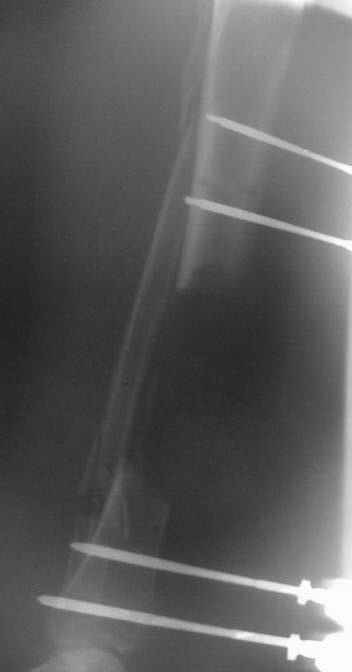

Dear Dr. Firas

You can do it like this also...